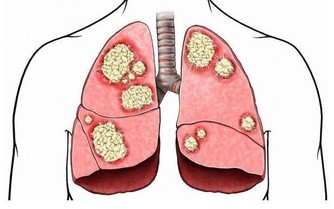

而隱睾患者睾丸未進入陰囊,長期留在腹腔和腹股溝管內,這些部分局部溫度高,

可導致睾丸生精細胞損害,影響精子的產生和生存,易導致不育。

此外隱睾由於生長環境改變以及發育上在障礙,容易發生惡變。